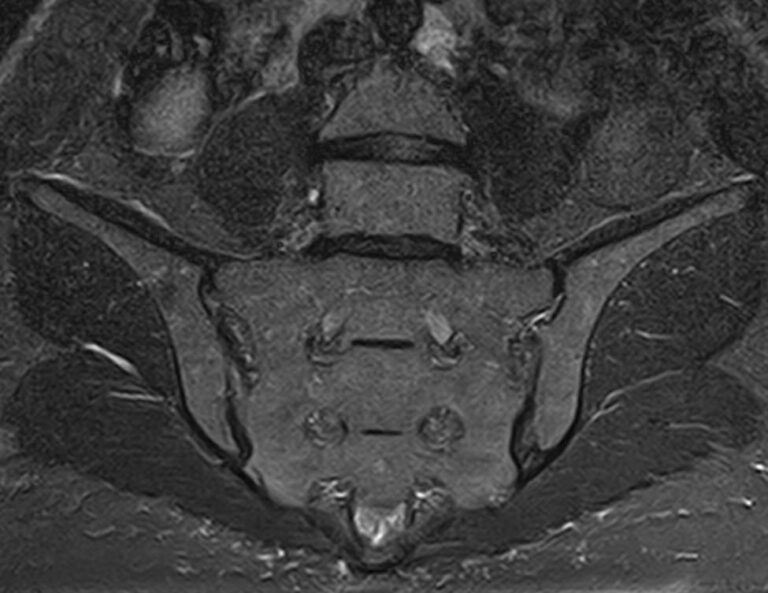

Крестцово-подвздошное сочленение – это крупный малоподвижный сустав, место соединения крестца и подвздошных костей, которое часто вовлекается в патологический процесс при травмах, дегенеративных поражениях, инфекциях и опухолевых заболеваниях.

С помощью МРТ можно диагностировать поражение крестцово-подвздошных сочленений на начальной стадии, когда другие методы не дают результатов. Такой патологией, в частности, является сакроилеит (воспаление крестцово-подвздошного сочленения), который часто становится причиной анкилоза (сращения) или нестабильности (патологической подвижности) сустава. Выявление сакроилеита на ранней стадии значительно улучшает прогноз в плане лечения и профилактики осложнений.

В клинике «Доступная медицина» диагностика патологии крестцово-подвздошных сочленений осуществляется на новейшем высокопольном томографе экспертного уровня TOSHIBA VANTAGE TITAN 1,5 Тесла. Аппарат проводит сканирование в различных плоскостях, делая срезы с шагом от 1 мм, затем с помощью компьютерных программ преобразует полученные данные в трехмерные изображения.

Что показывает МРТ крестцово-подвздошных сочленений

• Повреждения суставно-связочного аппарата в этой области;

• Дегенеративные и воспалительные процессы;

• Метастазы и опухолевые процессы. МРТ крестцово-подвздошных сочленений помогает выявлять новообразования на ранних стадиях, что не под силу многим другим методикам исследования. МРТ крестцово-подвздошного сочленения рекомендуют при наличии следующих жалоб пациента: